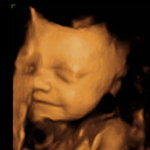

Mødregruppe: Oktober 2011